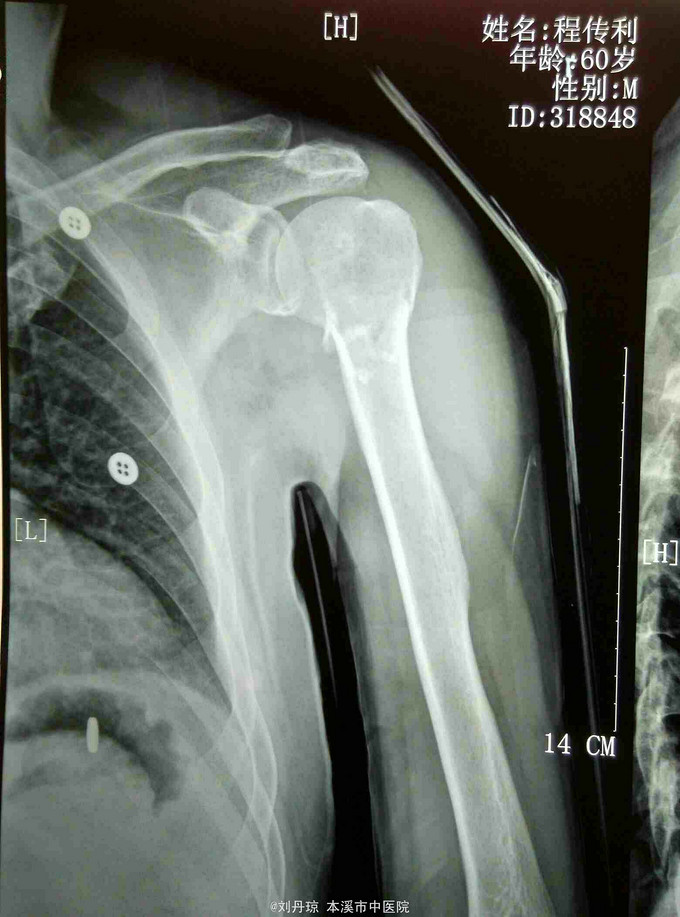

诊断:左肱骨近端粉碎骨折 治疗:手法整复,夹板固定。接骨丹口服。

随访1年。此四部分骨折,肱骨近端四个解剖部分完全分离,肱骨头移向后方,肱骨头血运破坏严重,容易发生缺血坏死。